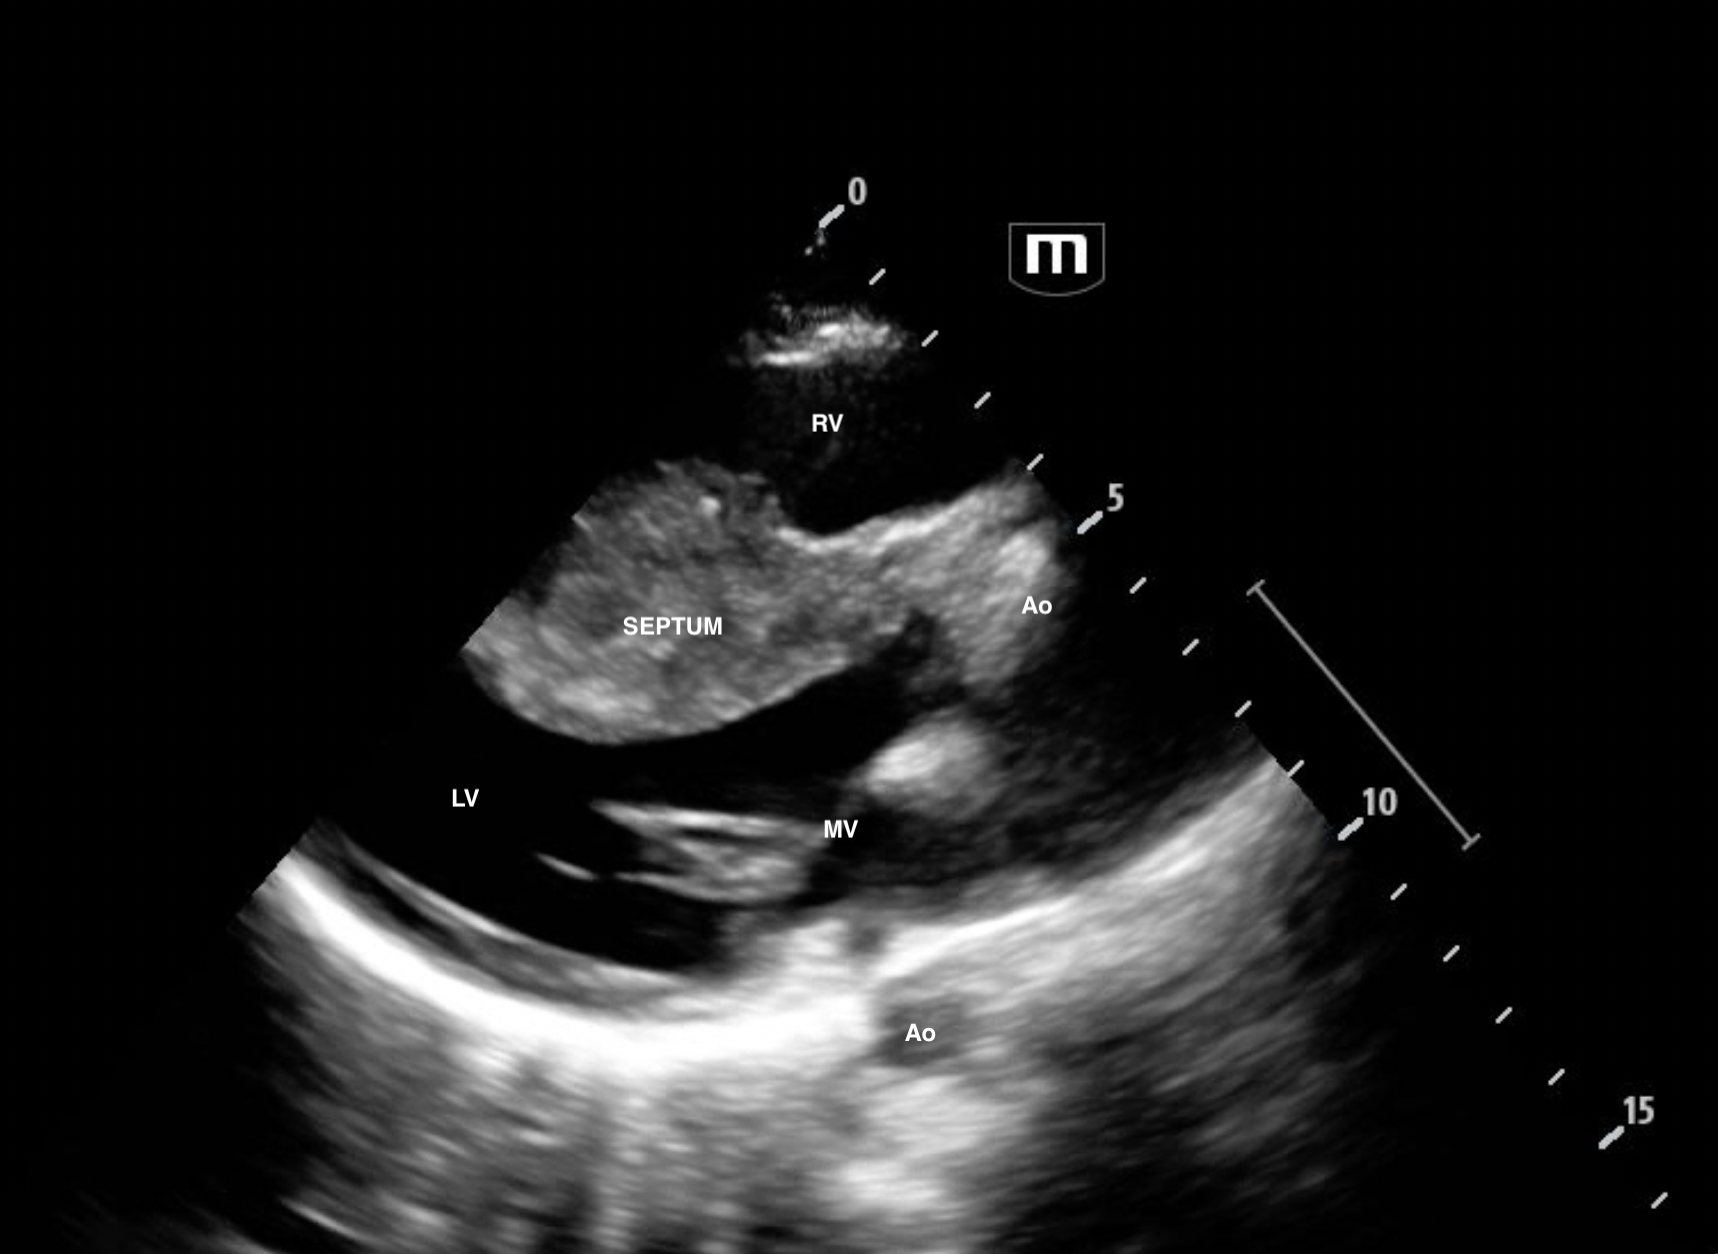

PLAx

The patient was admitted to cardiology. Formal echo revealed septal thickness of 3.2cm (normal <1cm). RV inflow was turbulent with a Vmax 4.2m/s (!!!!!!!) Mean 30mmHg and Peak Gradient of 69mmHg. For context, normal RV inflow ie flow across the tricuspid valve has a Vmax <0.7m/s.

Typically septal hypertrophy affects the LV side of the septum. But in this case, it's bulging into the RV.